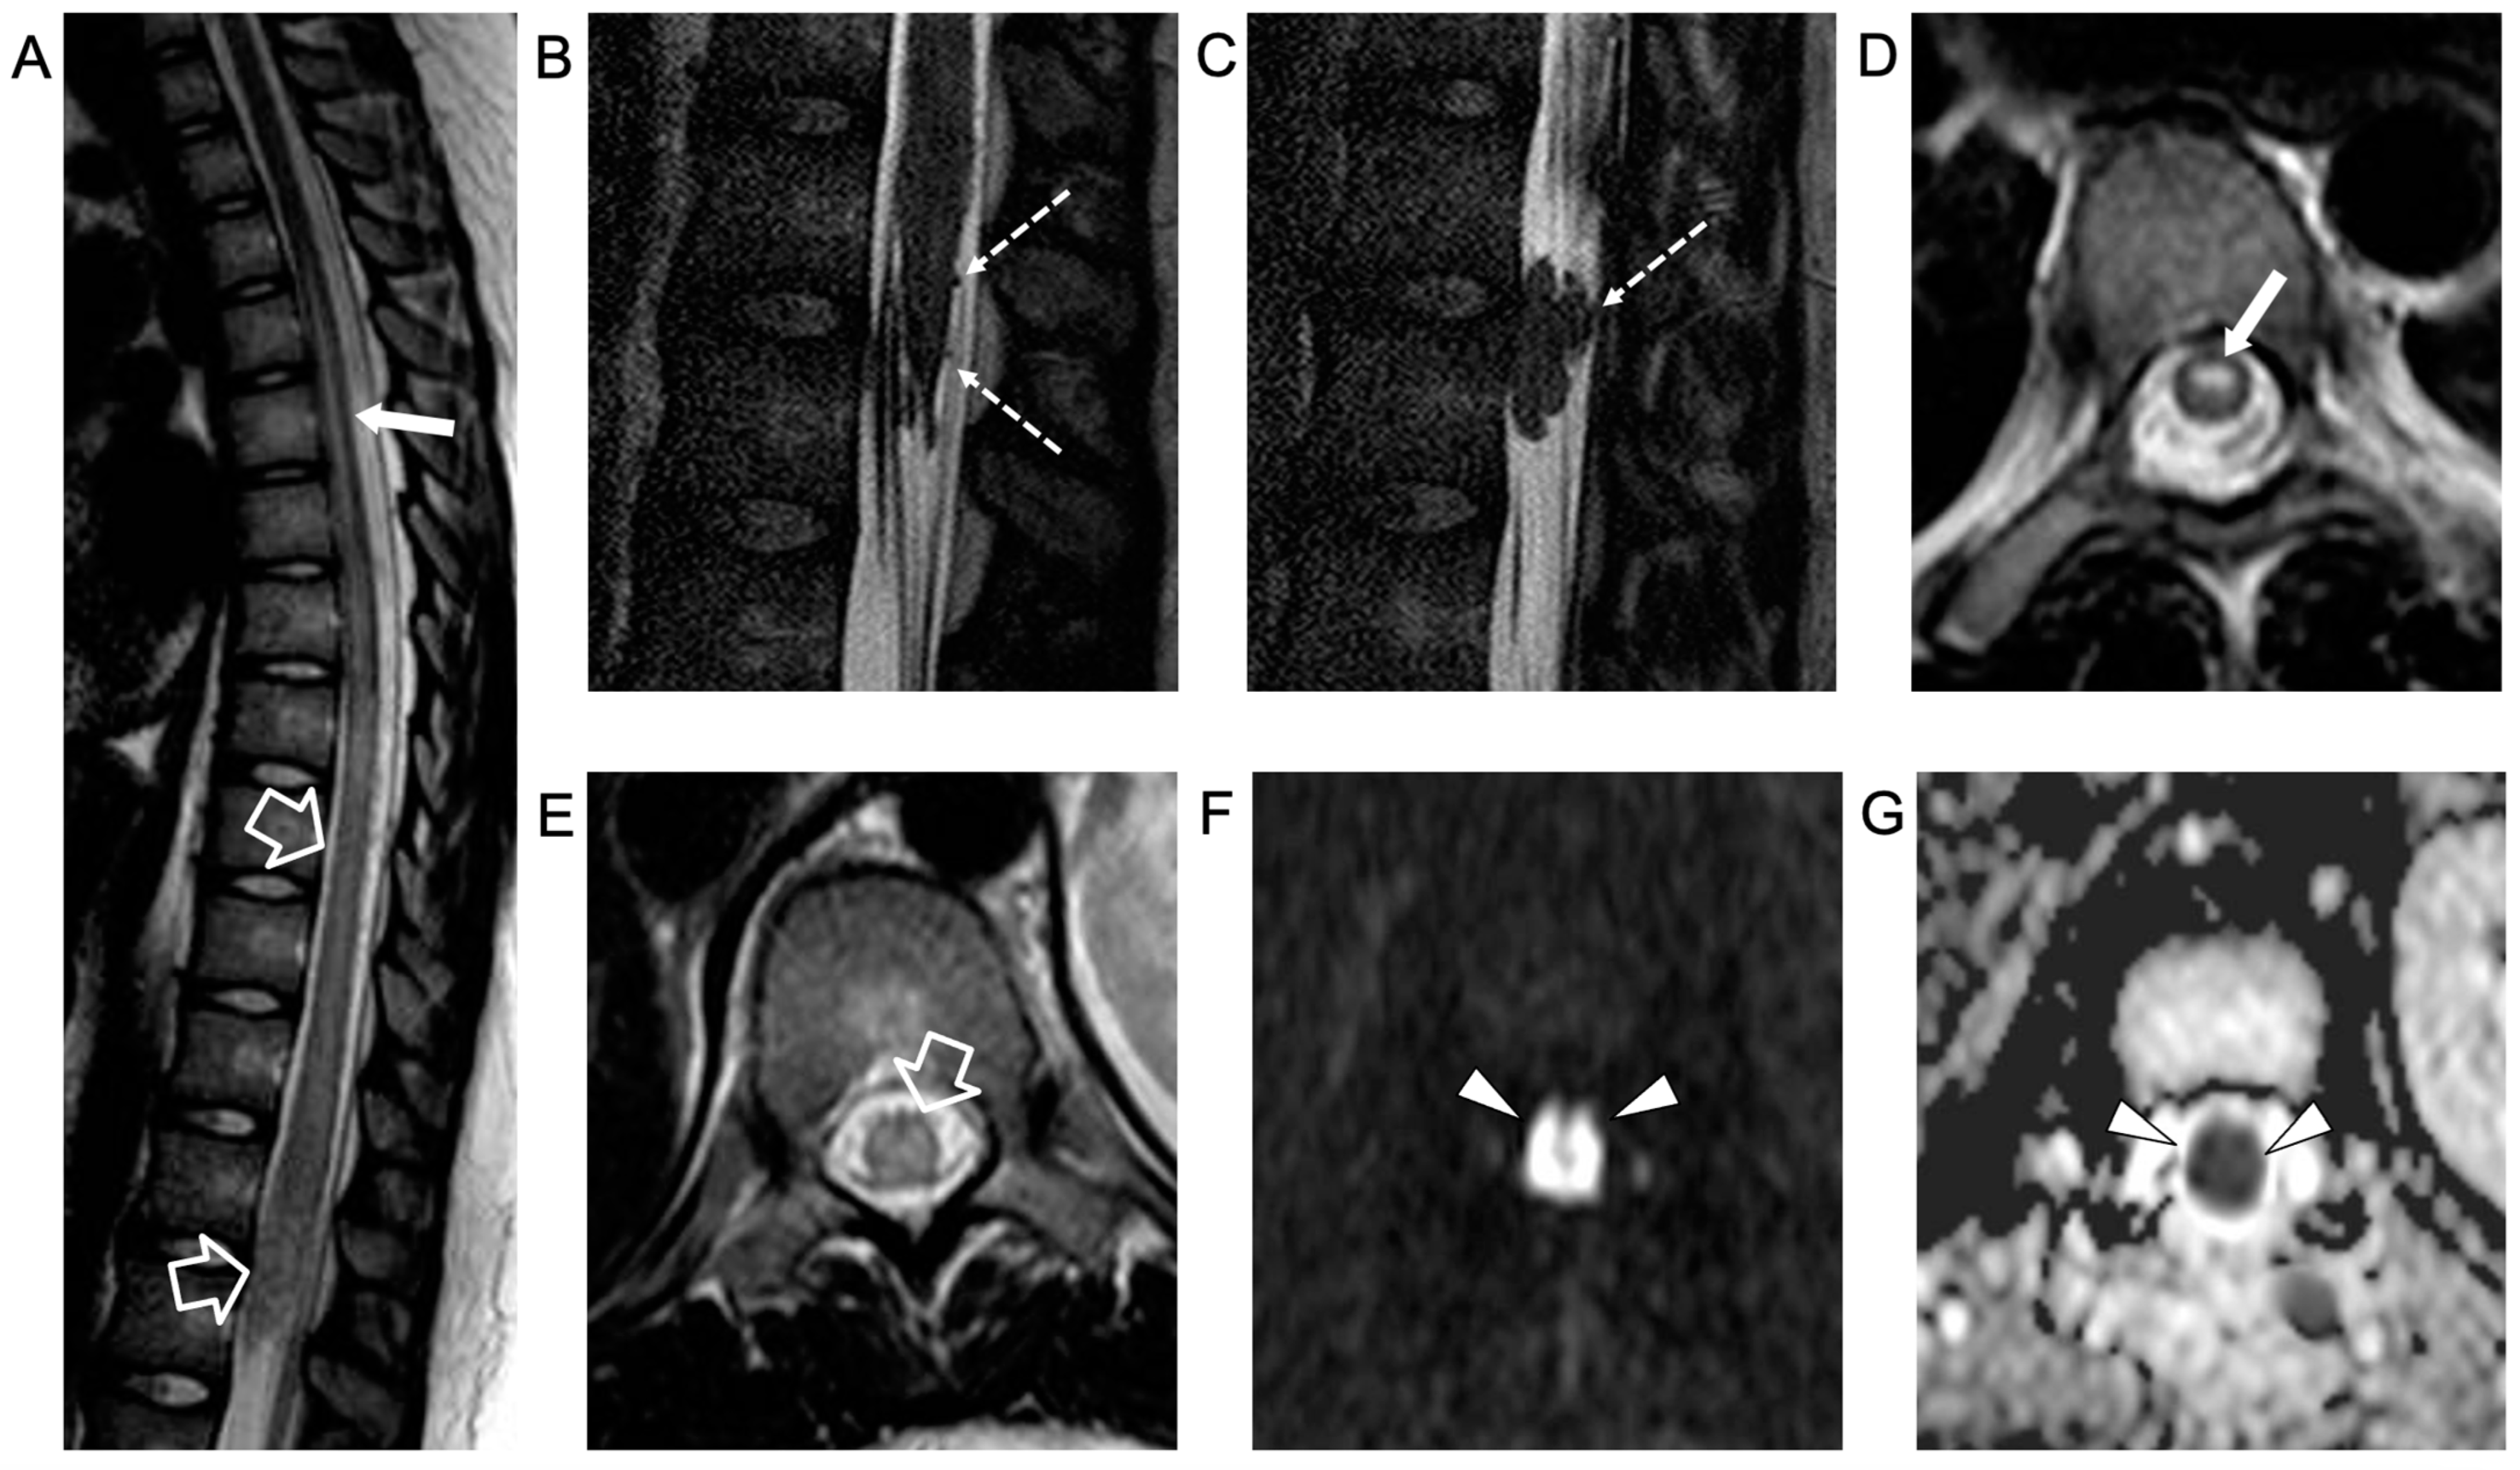

The electrophysiological study showed a low amplitude of somatosensory evoked potentials (SSEPs) in the lower limbs with the absence of F wave. Empirical therapy with ceftriaxone twice daily, 750 g acyclovir three times a day, 2 g/kg immunoglobulins, and 1 g/dose methylprednisolone (×4 bolus) was administered with a decrease in lumbar pain but no improvement in the strength of the lower limbs. A second spinal MRI, performed 5 days later, showed caudal extension of the acute transverse myelitis involving the conus medullaris, with more pronounced nerve root contrast enhancement, associated with an anterior spinal cord infarction (Figure 2)

Figure 2.

Contrast-enhanced spinal MRI performed 5 days after the clinical onset. Sagittal T2-weighted (A) and 3D driven equilibrium (DRIVE) (B,C) images; axial T2-weighted (D,E) images and diffusion-weighted image (F) with corresponding ADC map (G). There is a caudal extension of the T2 signal alterations involving the conus medullaris (empty arrows). Bilateral, symmetrical circular foci of high T2 signal are visible in the anterior horns of the spinal cord (i.e., owl-eyes sign) in the dorsal segment with a cranial extension to the D1 level (thin arrows). The spinal cord lesions are characterized by high signal on diffusion-weighted images with reduced ADC values (arrowheads) in keeping with a spinal cord infarction. In addition, there are several non-enhancing intradural extramedullary lesions along the cauda equina nerve roots and conus medullaris surface (dashed arrows).

An intradural extramedullary lobulated lesion was also noted at the level of the conus medullaris, with several similar small nodular lesions spreading along the cauda equina nerve roots and conus medullaris surface (Figure 2). A brain MRI demonstrated small subcortical gliotic changes in the right temporal lobe that remained stable in follow-up studies. Chest computed tomography (CT) and whole-body MRI were negative, as well as spinal digital subtraction angiography. A new CSF examination was performed: no atypical cells were detected but immunochemical tests showed barrier damage in the absence of oligoclonal bands. New microbiological tests and PCR on CSF and blood excluded some infective etiologies, in particular the presence of Cryptococcus, Aspergillus, Mycobacterium tuberculosis, Borrelia, Yersinia, Toxoplasma, and Bartonella. Antimicrobial therapy was shifted to 600 mg teicoplanin per day, subsequently substituted with 3 g ampicillin four times a day. For the suspicion of neoplastic disease, a biopsy of the extramedullary lesion was performed, revealing an ischemic lesion with perivascular inflammatory infiltrates and phagocytosis of uncertain significance, suggestive of an unspecified infective lesion. While waiting for the histological analysis, a second infusion of immunoglobulin, oral cyclophosphamide, and steroids was started for the suspicion of SLE-related transverse myelitis. An immediate postoperative spinal MRI performed 3 weeks after the onset revealed complete removal of the intradural extramedullary mass, while the spinal cord lesion and nerve root involvement were stable. The clinical picture worsened with progressive paraplegia and anesthesia of the lower limbs, urinary incontinence, and deterioration of neurophysiological findings. During the following weeks, plasmapheresis, cyclophosphamide, and immunoglobulin were administered and ampicillin was continued. Spinal MRI performed 6 weeks after clinical onset and showed a new acute ischemic lesion involving the inferior dorsal spinal cord and conus medullaris and additional small nodular lesions along the conus medullaris surface (Figure 3).